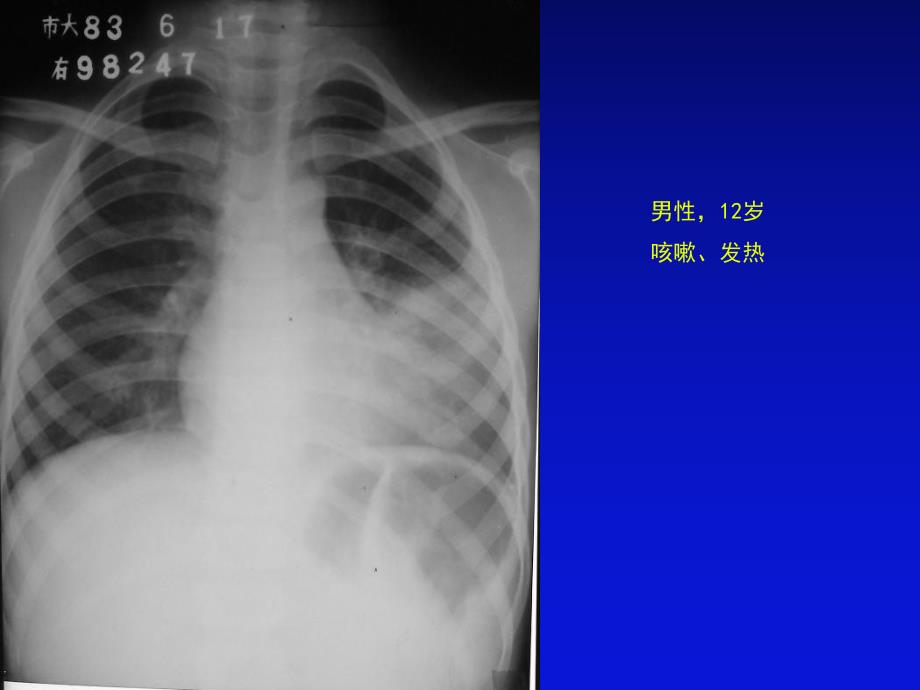

1、女性,24岁轻微咳嗽3天 种类和检查方法种类和检查方法:胸部后前位片胸部后前位片 描述描述:胸廓对称、无骨折和软组织肿胀;胸廓对称、无骨折和软组织肿胀;纵膈居中,无纵膈异常增宽表现;纵膈居中,无纵膈异常增宽表现;心影形态正常,心胸比例小于心影形态正常,心胸比例小于0.50.5;膈肌呈穹窿样,光滑、肋膈角锐利膈肌呈穹窿样,光滑、肋膈角锐利,无异常下移或上抬表现;无异常下移或上抬表现;双侧肺门对称、无异常肺门增大;双侧肺门对称、无异常肺门增大;两肺纹理清晰,无肺内异常密度表现。两肺纹理清晰,无肺内异常密度表现。初步诊断初步诊断:正常胸片正常胸片男性,12岁咳嗽、发热 种类和检查方法种类和检查方法:

2、胸部后前位片胸部后前位片 描述描述:左侧中下肺野中内带大片高密度影,密度不均,边缘模糊。左侧中下肺野中内带大片高密度影,密度不均,边缘模糊。初步诊断初步诊断:左下肺大叶性肺炎左下肺大叶性肺炎 种类和检查方法种类和检查方法:胸部后前位片胸部后前位片 描述描述:左肺中下野内中带可见沿肺纹理分布的散在斑片状致密影,密度左肺中下野内中带可见沿肺纹理分布的散在斑片状致密影,密度不均,边缘模糊。不均,边缘模糊。初步诊断初步诊断:左下肺小叶性肺炎左下肺小叶性肺炎 种类和检查方法种类和检查方法:胸部后前位片胸部后前位片 描述描述:右上肺野见大片类圆形致密影,病灶中央可见液平面,边缘右上肺野见大片类圆形致密影,